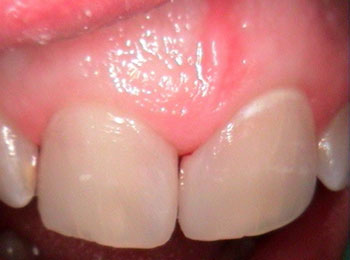

Bonding is an option for chipped or cracked teeth as well as an occasional alternative to veneers in certain cases. It is a process in which a series of composite materials of varying shades, tints, opacities and physical properties are used to precisely replicate any missing tooth structure. These next-generation materials are bonded to the tooth's surface, sculpted into shape, hardened, and then polished to match adjacent teeth.

Before bonding

After bonding